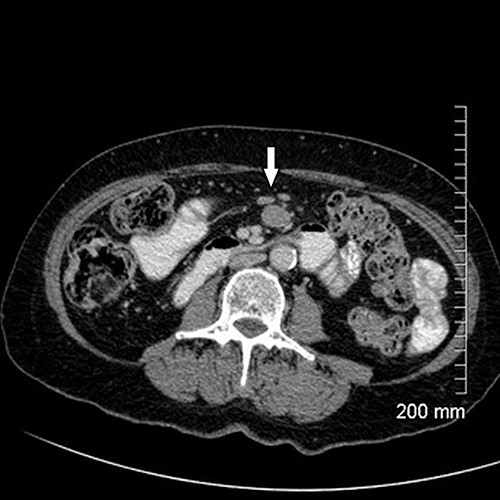

Upon assessment, her abdominal examination revealed tender epigastrium with no palpable mass. A plain abdominal radiograph appeared normal. Subsequently, a computerized tomogram (CT) of her abdomen and pelvis with intravenous contrast was performed, which showed dilated proximal small bowel with a 3-cm stricture and collapsed small bowel distal to the stricture. (Fig. 1). There was lymphadenopathy in the adjacent small bowel mesentery (Fig. 2). A small bowel resection (Proximal Jejunum) was performed through a midline laparotomy. The proximal jejunum was partially obstructed by a 3-cm tumour with multiple lymph nodes visible in the adjacent small bowel mesentery. Resection was done proximally at the duodeno-jejunal (DJ) flexure and distally 15 cm from the tumour in other to perform a satisfactory mesenteric lymphadenectomy (Fig. 3). The third and the fourth parts of the duodenum was partially mobilized and a side-to-side DJ anastomosis was performed.

Axial cut of CT abdomen & pelvis demonstrating strictured segment of small bowel (white arrow).